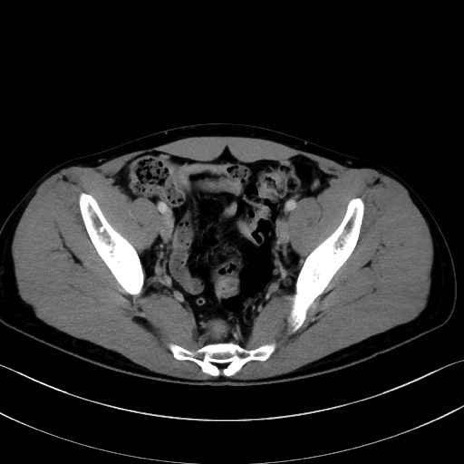

2. 腸腰筋群と骨盤底筋

大腰筋 (Psoas major)

腸骨筋 (Iliacus)